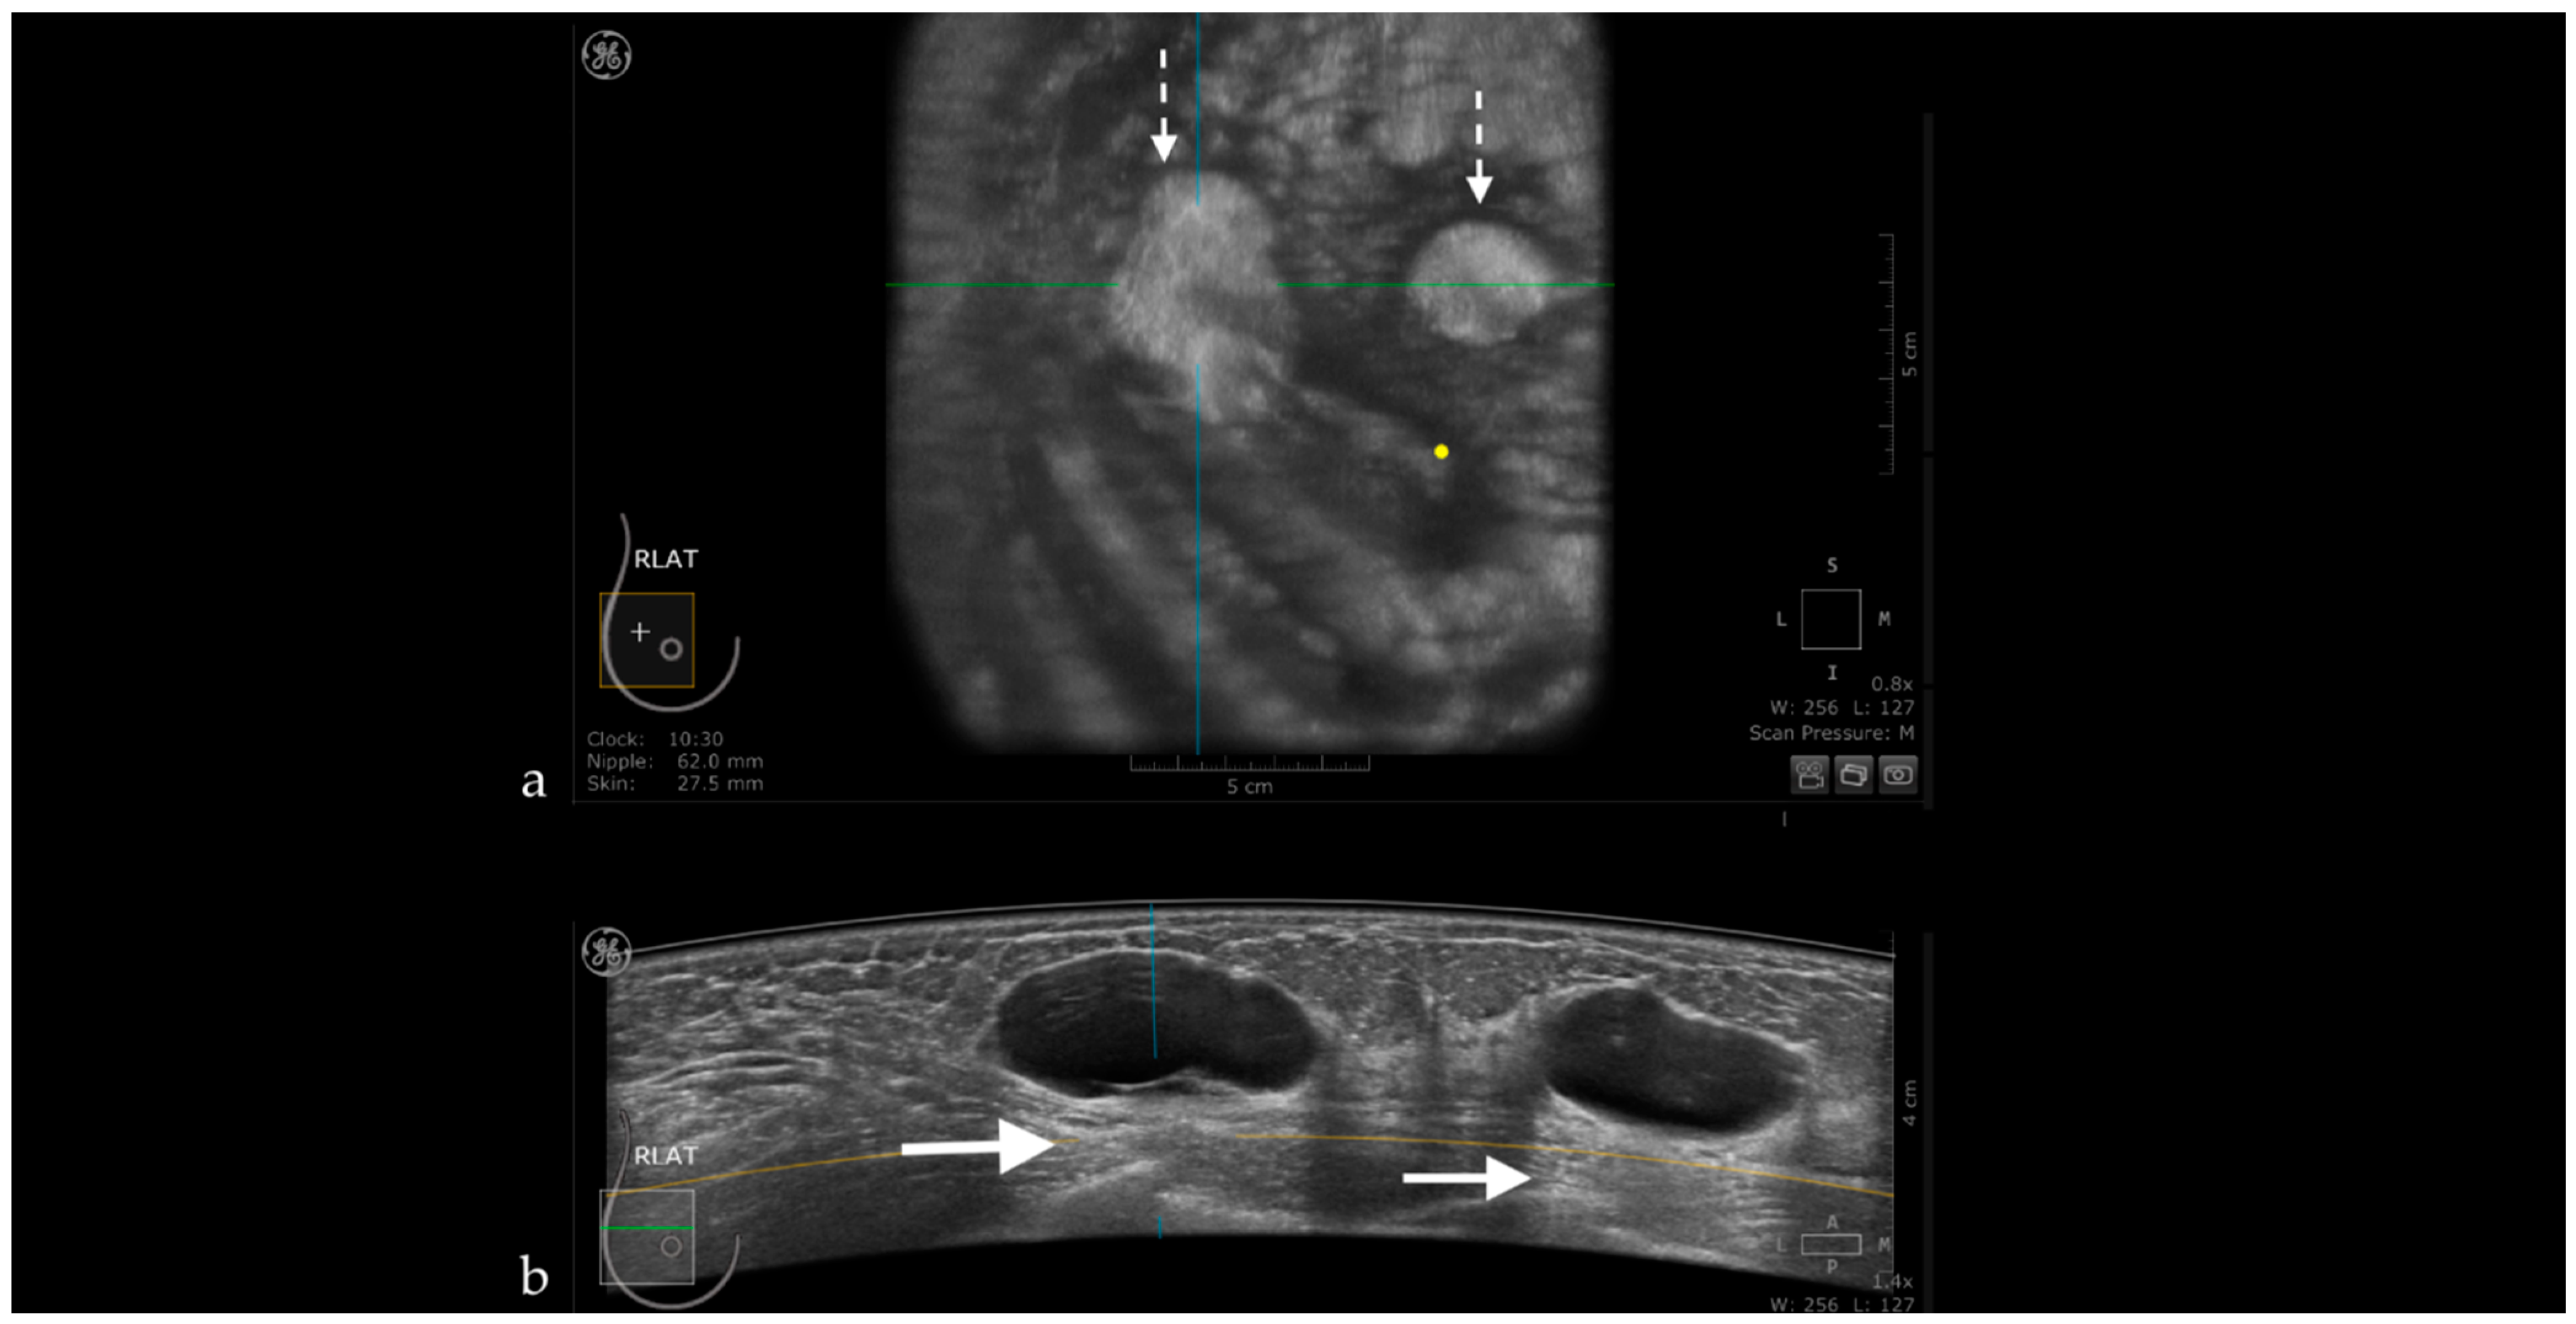

3.1. Technique and Artifacts

3.1.1. Limitations Related to the Technique

3.1.2. Artifacts

Artifacts Induced by the Use of Ultrasound Gel

Air Interposition

Insufficient Compression

Probe Motion Artifacts

Breathing Artifacts

Skip Artifact

Nipple Artifact

Attenuation Areas

White Wall Sign